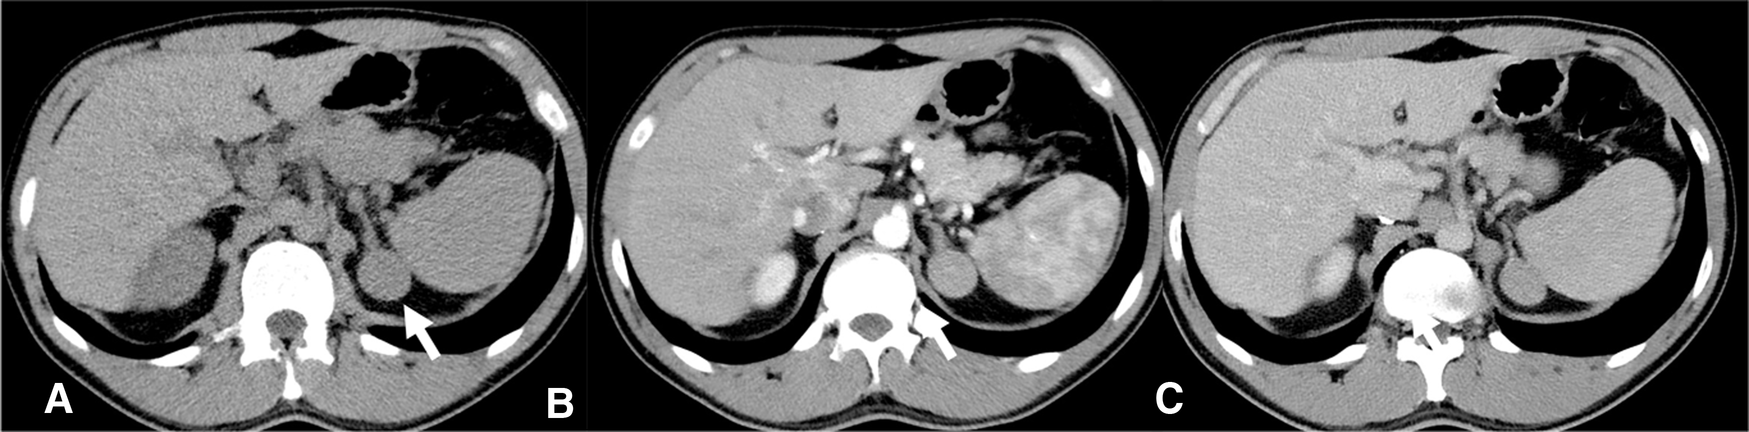

Figure 1

CT scan 2018- Homogeneous left adrenal mass with regular margins, (arrow), diameter of about 3 cm and a non-contrast CT density greater than 10 HU (A) not indicative of the presence of lipids. In the arterial (B) and venous (C) contrast phases, the mass presents a slightly heterogeneous appearance.

A 40-year-old man was seen at our clinic in summer 2020 for a left adrenal mass. At the age of 19, he had suffered from ACTH-independent Cushing syndrome, when a right adrenal lesion was detected at CT scan, leading to adrenalectomy. Histopathology was indicative of adrenocortical adenoma. Cortisol normalization occurred after surgery and follow-up visits were scheduled, with regular assessment of adrenal function and abdomen ultrasound imaging. In 2018, a CT scan had revealed a left adrenal mass with a maximum diameter of 3 cm (Figure 1). A diagnosis of adrenocortical adenoma with low lipid content was suggested. The absence of a previous CT scan to make a comparison, the size of the mass at that time (less than 4 cm), the mass homogeneity (absence of calcifications and hemorrhagic areas), the density (30–40 HU on average, below the limit of 43 HU), the regularity of the margins and the lack of a CT delayed phase (to evaluate the wash-out) had probably orientated the diagnosis. Hormonal evaluation disclosed normal adrenal function [ACTH 29 pg/mL, serum cortisol 450 nmol/L, serum cortisol after 1 mg dexhametasone 41 nmol/L, UFC 58 mcg/24 h, renin 7.8 µU/mL, serum aldosterone 100 pg/mL, aldosterone (ng/dL)/renin (µU/mL) 1.28, urine metanephrine 25.5 µg/24 h, urine normetamephrine 105.8 µg/24 h]. At an MRI scan performed in 2019, the lesion showed a minimal size increase, and a wait-and-see strategy was decided (Figures 2A–D). Qualitative analysis of axial MRI images in and opposed-phase (Figures 2A,B) revealed no signal drop inside the lesion. Retrospective quantitative analysis with ASII showed a 7.24% reduction in signal, which does not meet the criteria for adenoma, in T2 MRI images with fat suppression the lesion was isointense. Overall, MRI features were not typical for an adenoma (9). Probably the homogeneity of the lesion, the minimal growth and the previous adenalectomy explain the ‘wait-and-see’ strategy.

At CT scan or MRI, about 30% of oncocytomas may display a central fibrous scar, resulting in the so-called ‘spoke wheel’ pattern (14), not observed in our case. In our patient, the adrenal mass was homogeneous, measured less than 4 cm (in the first CT and MRI), and had regular margins. Although lipid content was not typical of an adenoma, and areas of hyperintensity in T2 (possible necrosis) and T1 (possible hemorrhage) were suspicious, the lesion did not display features leading to a definite characterization. Radiologic features of adrenocortical oncocytic neoplasms are not pathognomonic (11, 15). The oncocytic variant of ACC is similar to classic adrenocortical malignant tumors, whereas oncocytomas differ from adrenocortical adenomas (from 20 to 40 Hounsfield Units and inhomogeneous enhancement versus less than 10 Hounsfield Units at CT scan) (16, 17).